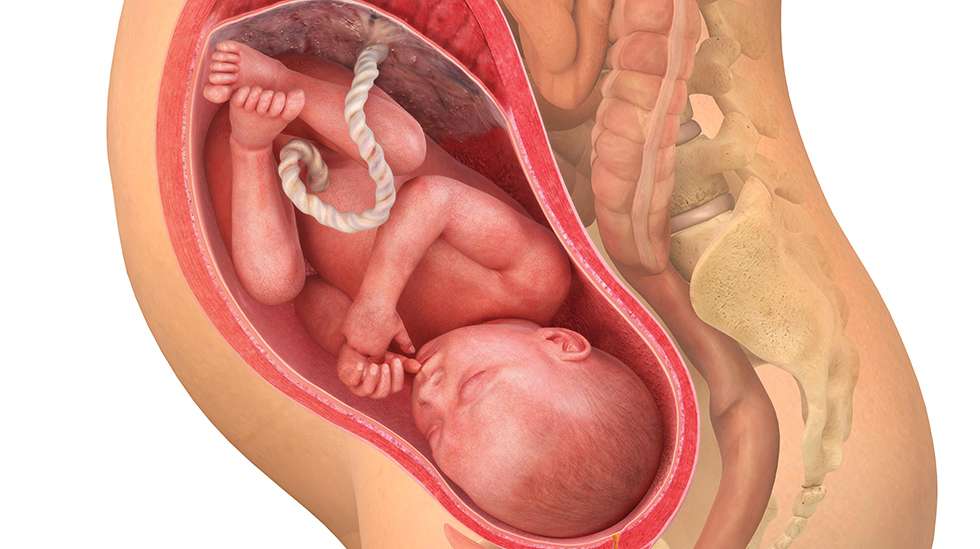

35. raskausviikko – lapsi avaa silmänsä ollessaan hereillä ja sulkee ne nukkuessaan, vaikkei vielä nääkään muuta kuin pimeyttä.